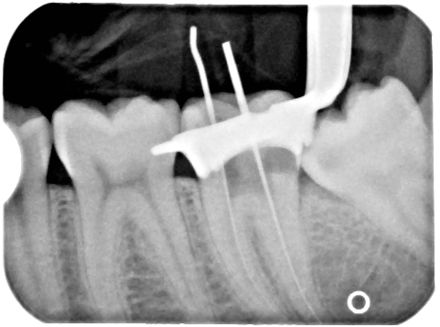

Xray of a Root Canal Operation — Image from Wikipedia

Sometimes a nerve in a tooth becomes damaged by trauma or tooth decay. Root Canal Treatment or Endodontic therapy or root canal therapy is a sequence of treatment that offers an alternative to tooth extraction.

In this procedure the nerve or dental pulp of the tooth is removed. This is done over several appointments and a temporary filling is used between these appointments to protect the tooth.